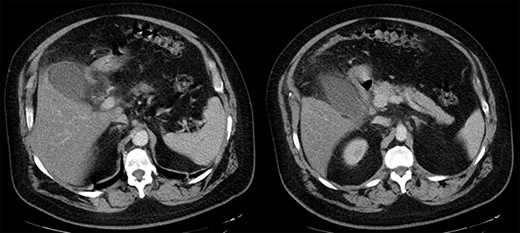

The patient was, initially, admitted to the COVID-10 department and received empiric antibiotic coverage (Piperacillin and Tazobactam), thromboprophylaxis (enoxaparin 4000 IU) and bronchodilator agents (budesonide and ipratropium). Upon the third day of admission, due to the ongoing fever and the increase in the inflammatory markers (WBC 15.80 K/μl, CRP 297.07 mg/L, ferritin 821 ng/ml), a chest and abdominal computed tomography (CT) scan were performed. Imaging confirmed the presence of marked gallbladder dilatation and wall thickening, combined with free peritoneal fluid and pericholecystic omental involvement (Fig. 2).

Abdominal CT scan. Marked gallbladder dilatation and wall thickening, combined with free peritoneal fluid and pericholecystic omental involvement.